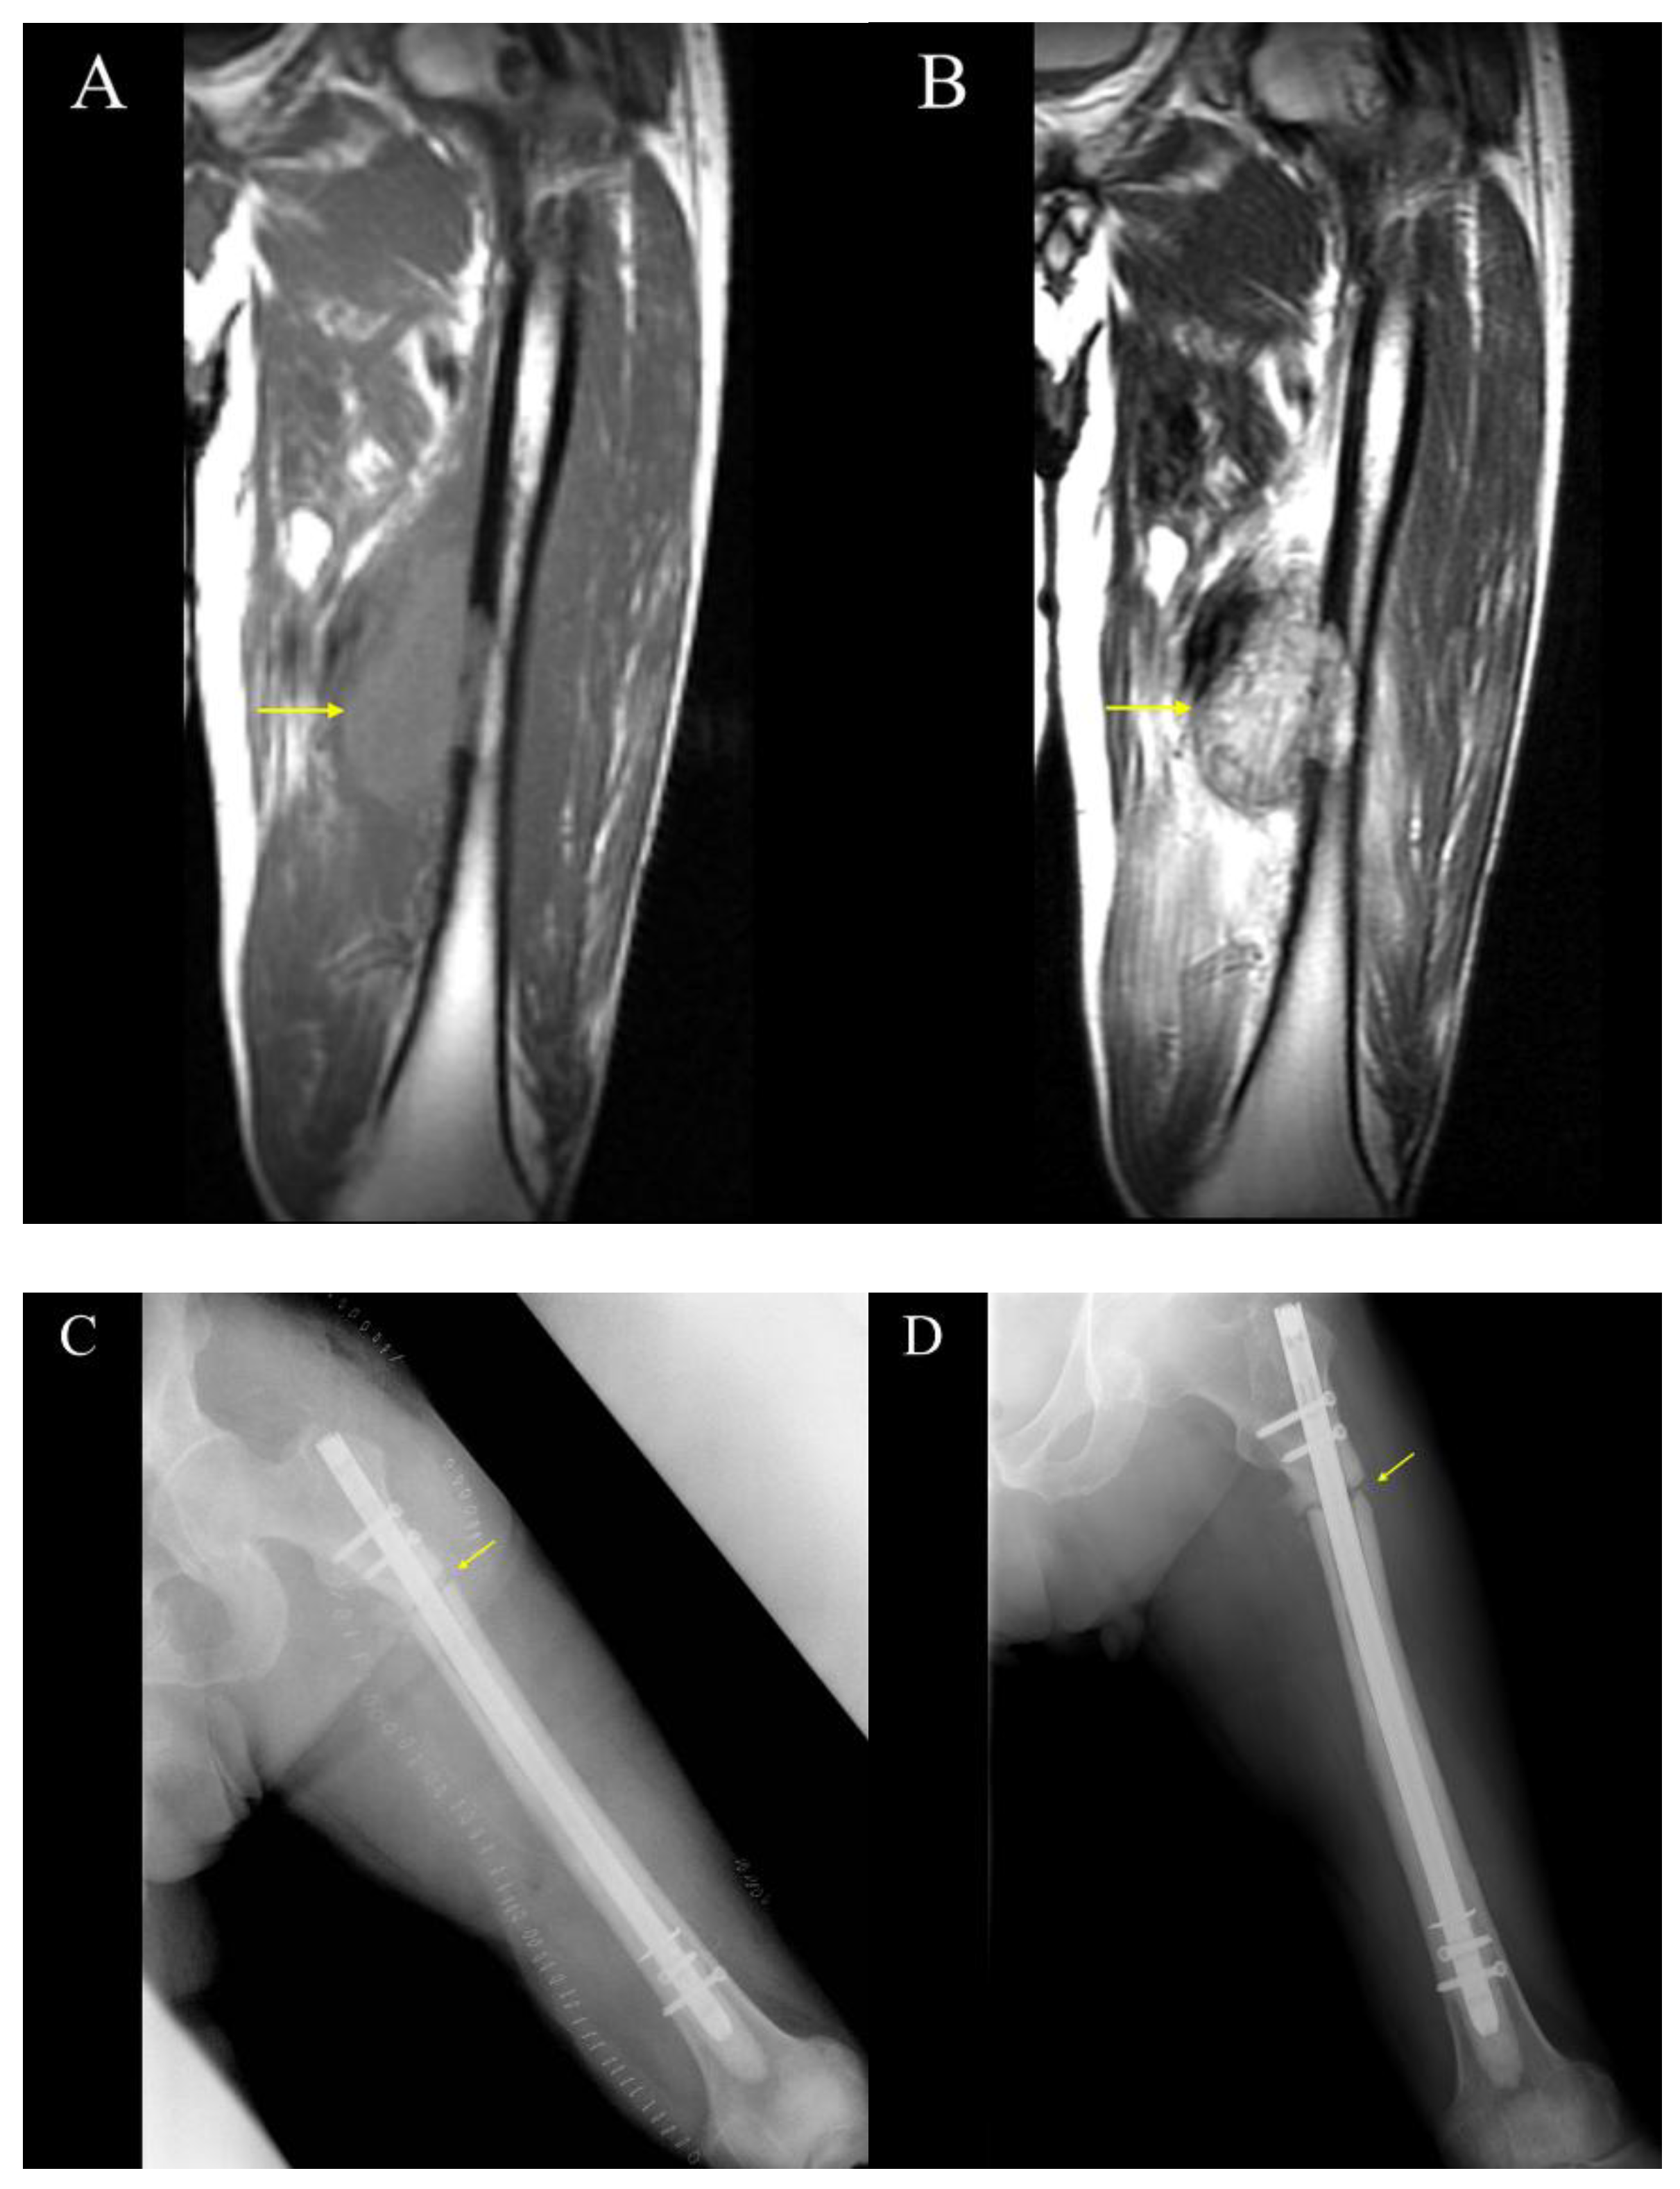

3.3. Cases